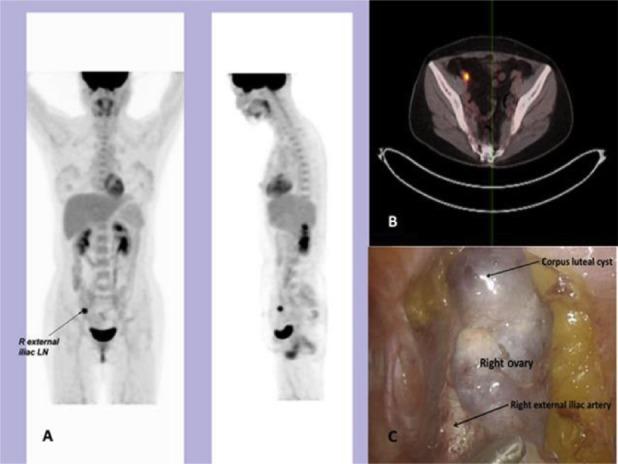

A 47 year old patient with a G3, FIGO stage 1A endometrial cancer was treated by hysterectomy. Her two ovaries were conserved because of the pre-operative diagnosis of endocervical cancer. On follow up PET-CT follow up investigation, she had a benign ovarian corpus luteal cyst mistaken as a metastatic pelvic lymph node which was later removed and proven benign histologically. This paper is to raise the clinical awareness of possible false positive PET finding from a benign ovarian cyst, such that a misinterpretation of "recurrence" as in this case can be avoided.